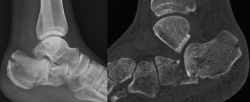

Figura 5. Varón de 37 años con fractura del calcáneo de Sanders de tipo IIB tras caída de altura. En la imagen de la tomografía computarizada se observa hundimiento de la zona lateral de la subastragalina posterior y un trazo posterior “en lengua”. Ángulo de Böhler precirugía de 8,5°.

A la hora de corregir el varo-valgo y la longitud del calcáneo colocamos un pin Steinmann o aK de 3,0 o 4,0 en la tuberosidad posterior y damos angulación varo o valgo (Figura 4) según necesite cada caso y siempre comprobando con la fluoroscopia (proyección axial). Una vez conseguida la angulación correcta, se fija de forma definitiva con 2 tornillos canulados de posterior a anterior (Figuras 5 y 6).